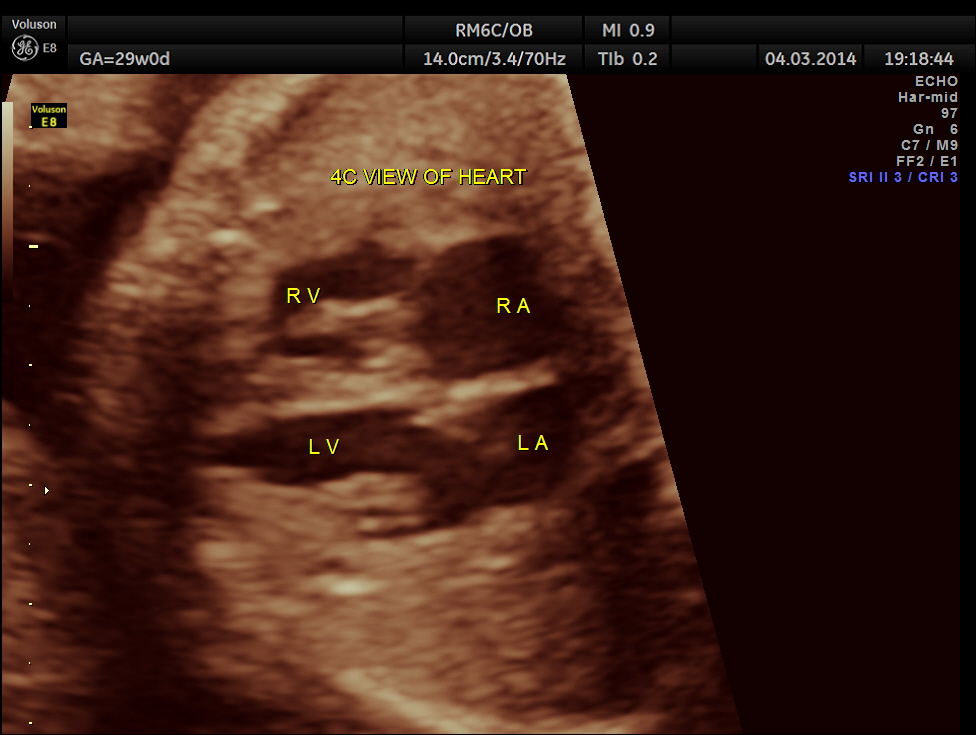

Images of the other organs are given below.